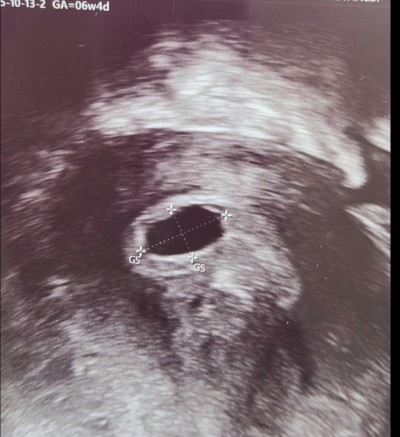

Merhaba, 6+4 vajinal ultrason goruntusu. Doktor anormal bir durum yok 2 hafta sonra gel dedi. Ama içim rahat etmedi. Sol tarafta bir karalti görüyorum yolk sac olabilir mi anlayan varmi? Kese çapı 1 cm, haftasına gore geri mi? Daha önceki hamileliklerimde bu zamanlarda kalp atışı duymuştum ama suan bebek görünmüyor, gec dollenme de olabilir supriz bir gebelik oldu. 5+4 te 2 kese goruntusu vardı sonraki hafta birinin ilerlemesi durmuş, o gün beta 3200 du.Upload failed: [object Object]

Gebelik haftası 7